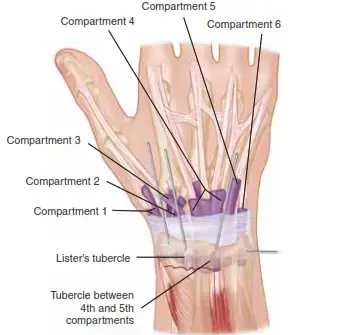

أمراض المفاصل دليل شامل لأمراض ومشاكل اليد: التشخيص والعلاج مع الأستاذ الدكتور محمد هطيف

دليل شامل لأمراض ومشاكل اليد: التشخيص والعلاج مع الأستاذ الدكتور محمد هطيف

انكماش دوبويتران هو تليف تدريجي في اللفافة الراحية يسبب انثناء الأصابع. يبدأ العلاج بالمراقبة، وقد يتطلب التدخل الجراحي في المراحل المتقدمة لتحسين وظيفة اليد ومنع الضرر المفصلي، تحت إشراف متخصصين لضمان أفضل النتائج.